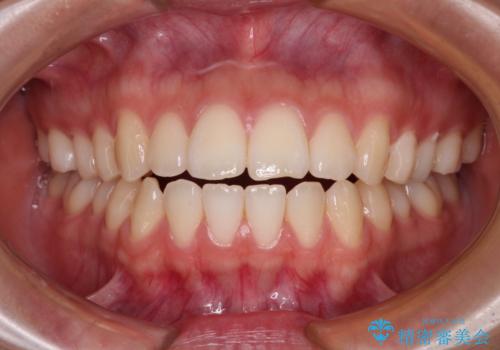

開咬をワイヤー装置で矯正治療

担当医 藤巻太一朗

オープンバイトをインビザラインで矯正治療